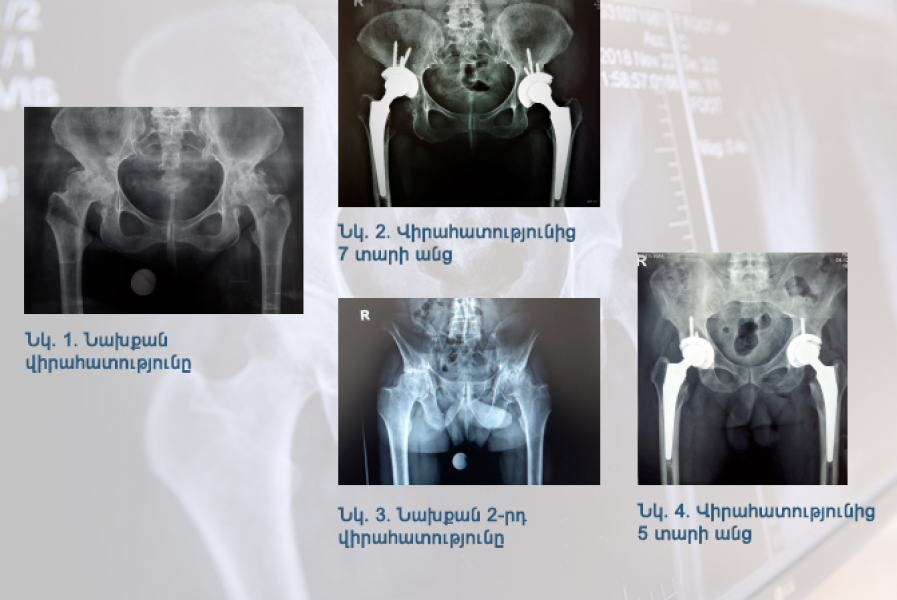

Կլինիկական դեպք. էնդոպրոթեզավորում` փսորիատիկ արթրիտի և երկկողմանի կոքսարթրոզի ժամանակ

Էնդոպրոթեզավորման մեթոդների զարգացման շնորհիվ կոքսարթրոզների վիրահատական բուժման մեջ բավականին առաջընթաց է գրանցվում․․․